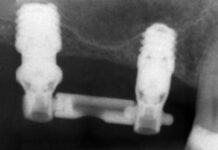

In questo articolo vengono descritti due casi clinici caratterizzati da eruzione ectopica dei primi molari permanenti mascellari trattati con tempistiche differenti.

This article presents two clinical cases of maxillary first permanent molars exhibiting ectopic eruption, treated at different stages of dental development.